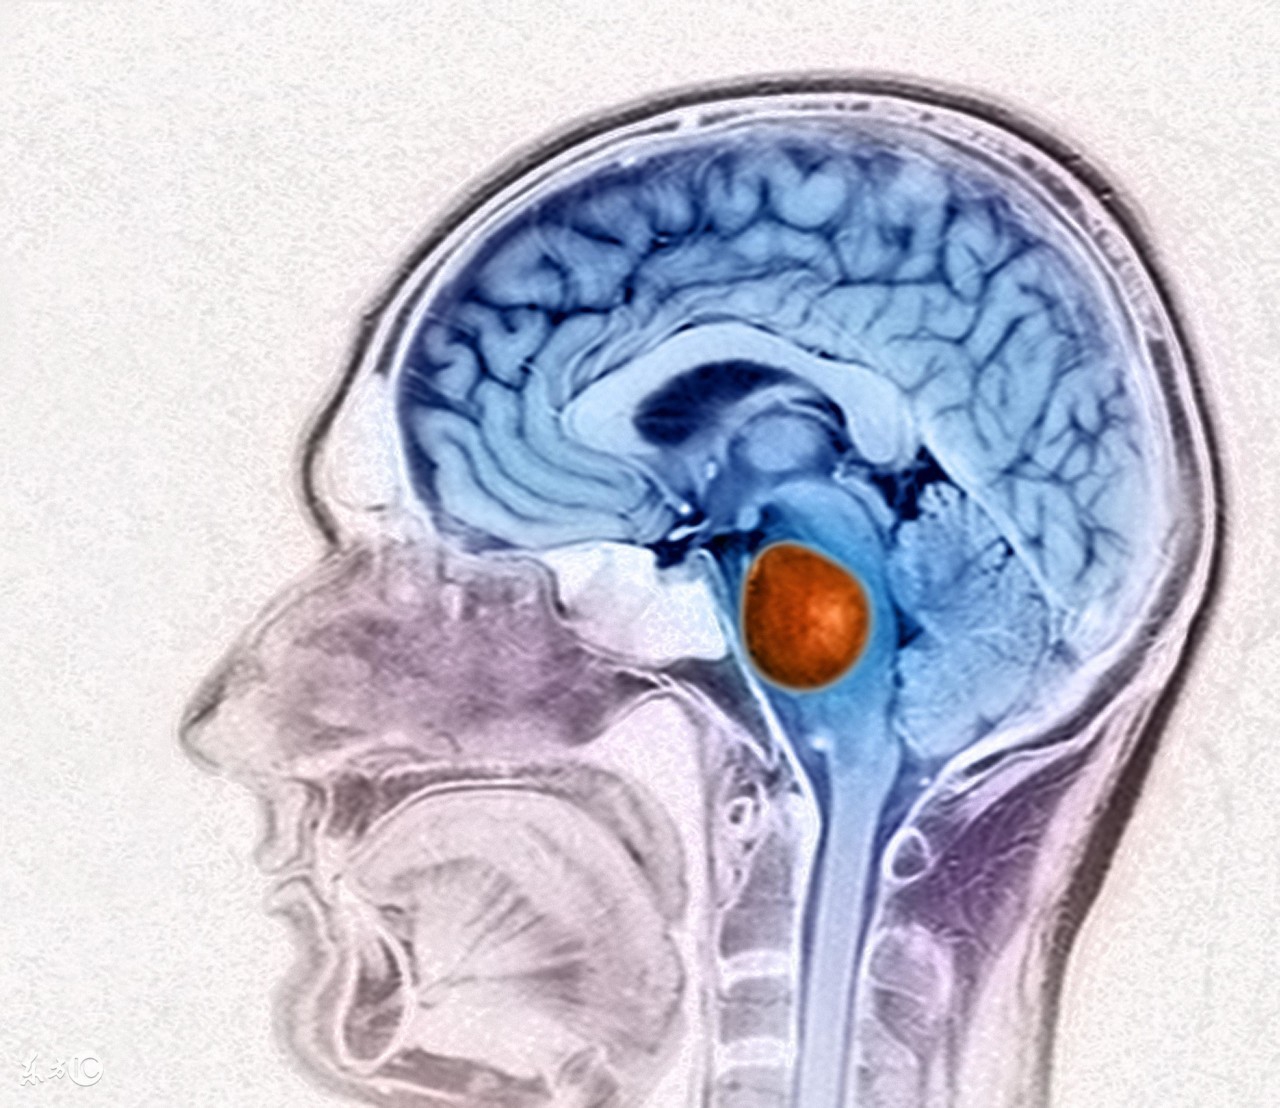

脑瘤是一种会严重影响患者脑神经系统的疾病,生活中,患有脑瘤的患者并不在少数,由于这种疾病对于患者的危害非常大,所以及时有效的治疗是很重要的,随着我国医学技术的不断进步,治疗脑瘤的方法是有很多种的,但是如果这种疾病发展到晚期应该怎么办呢?下面我们就来根据这个问题来进行一下详细的介绍。

二、放射治疗

适用于脑转移瘤及各种原发脑瘤的术后治疗,如神经胶质瘤、垂体腺瘤、生殖细胞肿瘤及脊索瘤等。手术不能彻底切除的脑瘤,术后辅以放射治疗可以延迟肿瘤复发。脑转移瘤的放射治疗常可以获得较好的姑息效果,可以减轻症状,提高生存质量,延长生存时间。对放射线敏感的肿瘤,手术困难时可首选放射治疗。